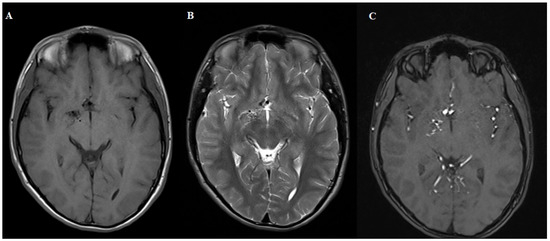

Figure 1. MRI T1 (A), T2 (B) and 3D TOF (C). Sequences demonstrating normal brain parenchyma with a tangle of small blood vessels without a visible draining vein. The patient was referred for digital subtraction angiography.

Diagnostics 15 01333 g001